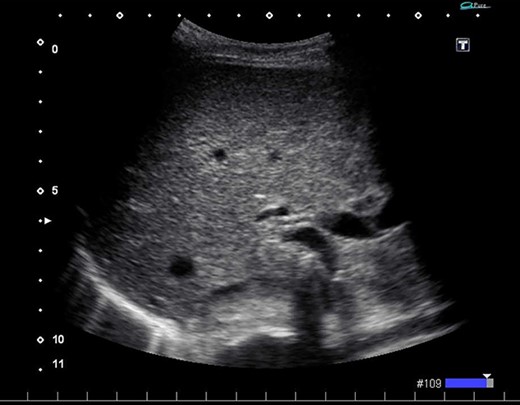

We found a gangrenous gallbladder with 180° clockwise rotation along the longitudinal axis and performed cholecystectomy (Fig. 3). Intraoperative exploration revealed no ischemic findings in other visceral organs. On US obtained immediately after the operation, the hyperechogenic foci disappeared (Fig. 4). Her postoperative course was uneventful, and she was transferred to the rehabilitation hospital on the 12th day. Histology confirmed a necrotic gallbladder without neoplastic changes.

Ultrasonography after surgery shows no findings of PVG in the liver.